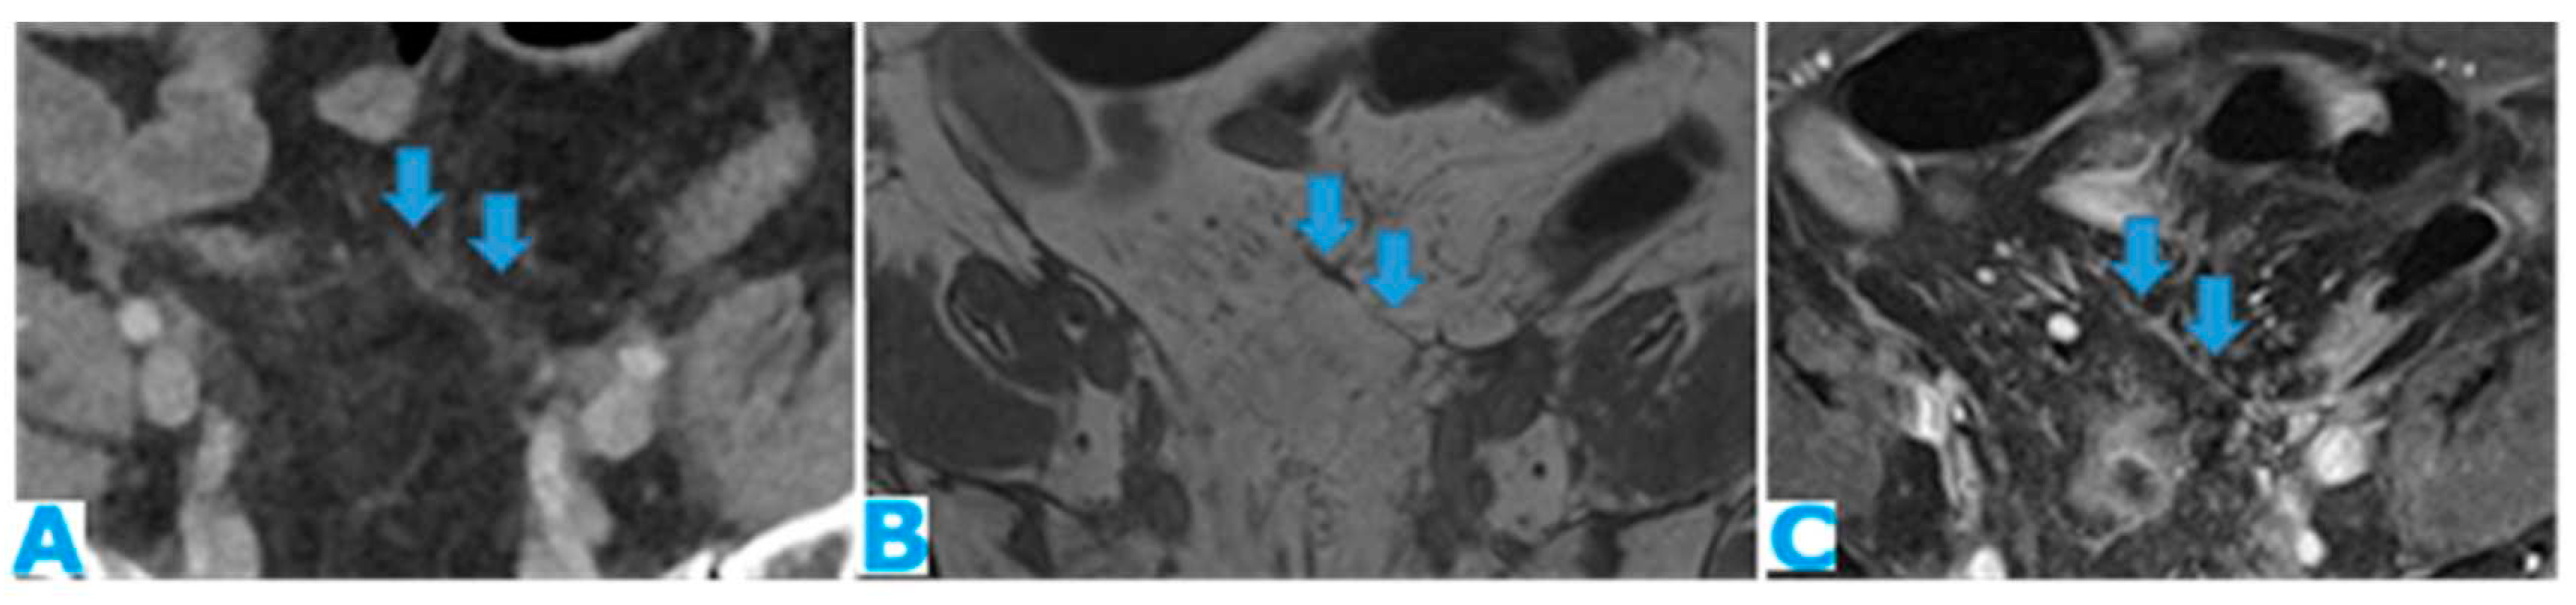

Figure 24.

Axial CE-CT (A), axial T2WI (B), axial CE portal phase FS T1WI (C). PC from endometrial carcinoma: Deposit seeding within the mesenteric leaves.